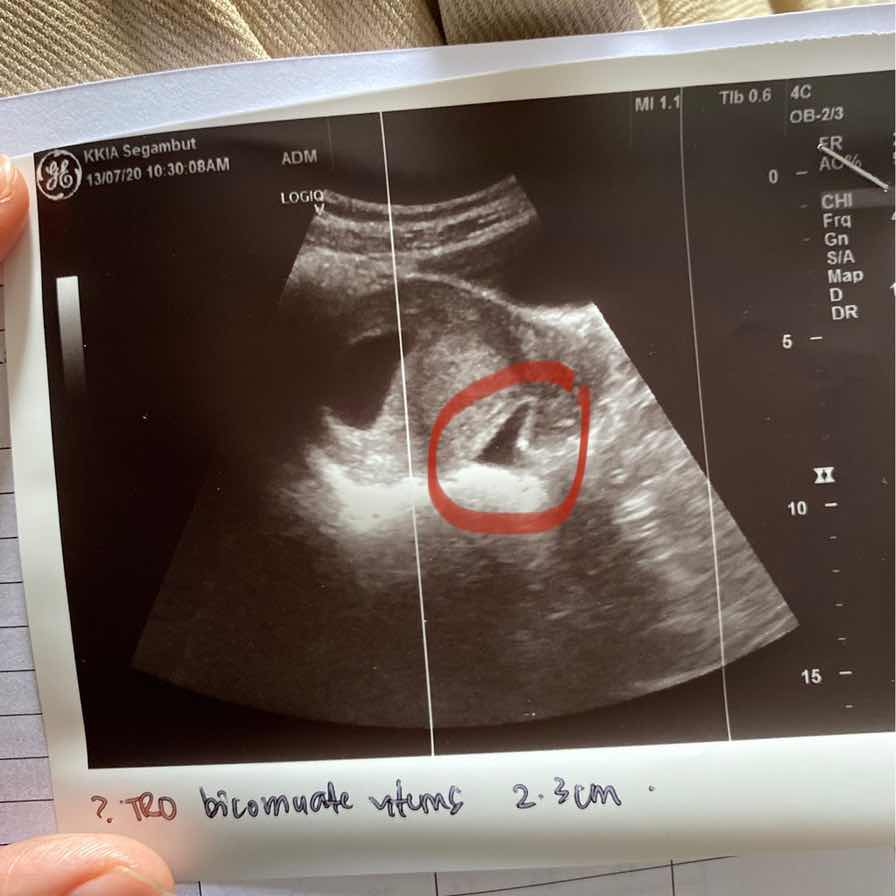

Something not sure sebelah kantung baby